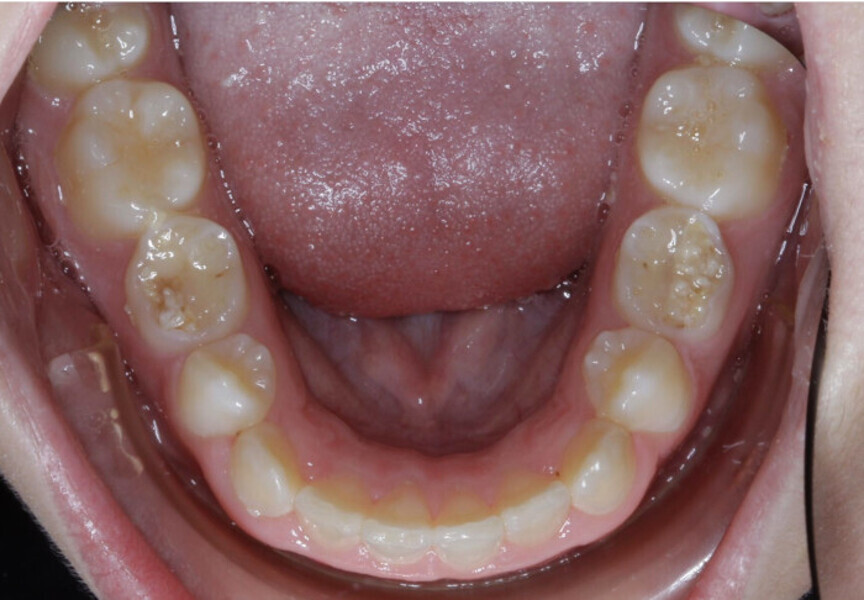

New Age orthodontics and orthopaedics with temporary anchorage devices